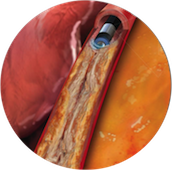

このためほとんどの治療において、バルーンでの拡張後にステント(金属でできた網状の筒)を留置します。

ステント留置はリコイル現象を防ぎ、血管の解離も修復することができるすぐれた治療法です。

しかしステント治療を行っても治療後6か月程度するとステントの中に新生内膜と呼ばれる膜が過剰に発達してしまい再度狭窄してしまう場合があります(再狭窄現象)。

この再狭窄現象を抑制するべく登場したのが、現在冠動脈治療の主流となっている薬剤溶出性ステントです。ステントの表面に薬を塗布してあり、これが少しつ溶け出すことにより再狭窄を強力に抑制します。 初代の薬剤溶出性ステントはステントに血栓が集まり急激に閉塞するステント血栓症や、1年以上たって起こる遅発性再狭窄などの問題が指摘されていました。

しかし現在はこれらの問題を解消すべく改良された新世代薬剤溶出性ステントが複数使用可能であり、 当院では主にこの新世代の薬剤溶出性ステントを用いて治療を行っています。